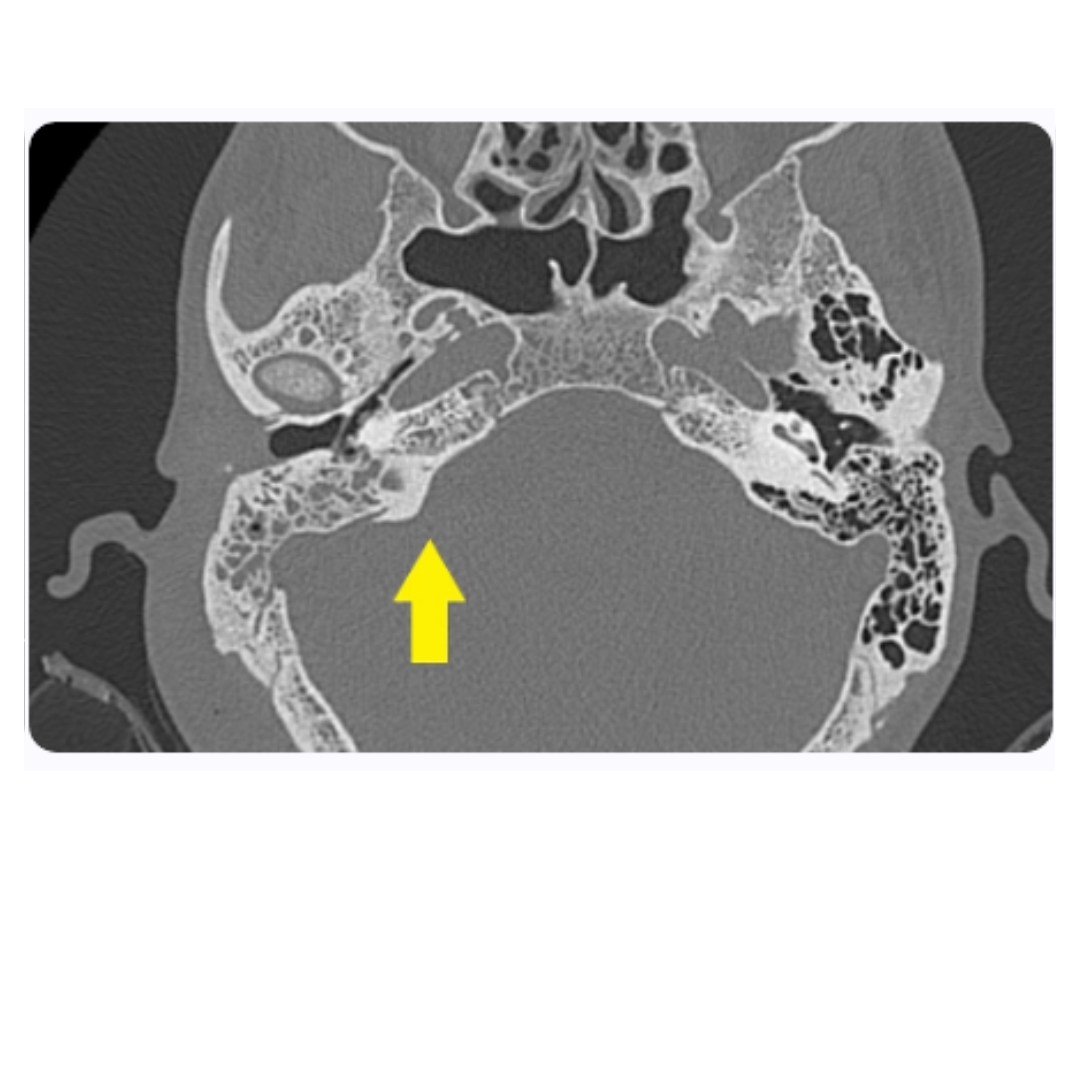

Tomografía computarizada de tórax

La tomografía computarizada (TC) de tórax permite la evaluación de complicaciones pulmonares en pacientes con LLA. Especificidades como infiltrados pulmonares o la presencia de masas mediastínicas pueden ser indicativos de enfermedad agresiva o complicaciones infecciosas. Por lo tanto, la TC es un componente indispensable del arsenal diagnóstico, proporcionando información valiosa para el manejo integral del paciente.